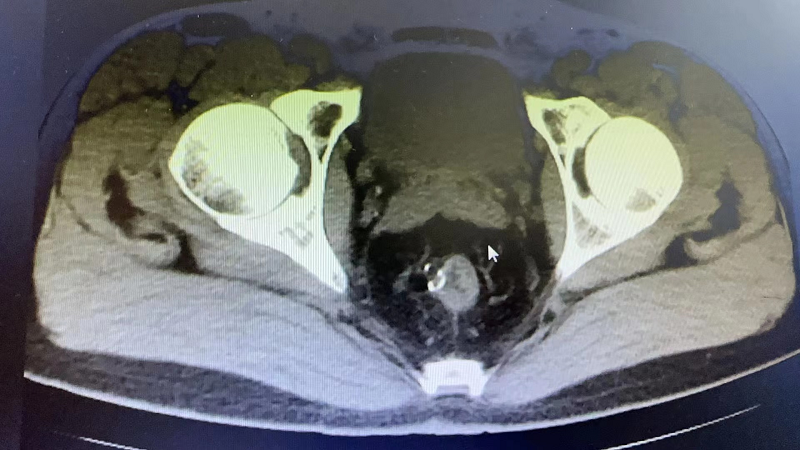

近期,73岁的J大爷比较烦恼,他出现了排尿困难、疼痛症状,这严重影响了J大爷的生活。在家人的陪伴下,J大爷辗转当地多家医院,但都因为J大爷有多种基础疾病未能如愿,最终在亲戚的介绍下来到av片 泌尿外科就诊。通过接诊医生的详细询问病史并结合相关检查,诊断J大爷为:膀胱结石、泌尿道感染,建议J大爷住院行微创手术治疗。

经询问和检查,J大爷有重度贫血、慢阻肺、呼吸衰竭、冠心病支架植入术后等既往病史,泌尿外科高茂主任特邀多个专科主任前来参加会诊,各位专家积极发言,围绕J大爷的基础疾病、手术风险等展开讨论,最后确定适合J大爷的诊治方案。

手术由泌尿外科高茂主任亲自操刀,在麻醉科、手术室的倾力配合下,一小时就为J大爷完成尿道内镜下膀胱结石钬激光碎石术,成功解决了约3.0*2.0cm的大结石。